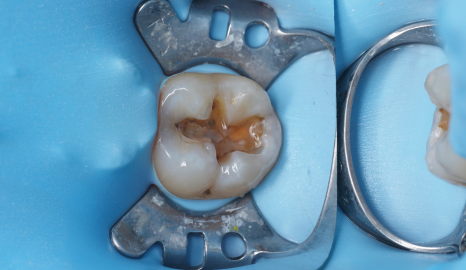

처음 내원하셨을 때 겉보기엔 레진 치료 후

살짝 불편한 정도로 보였습니다.

하지만 정밀한 진단을 위해 방사선 촬영과

근관 검사를 진행해 보니 문제는

그리 단순하지 않았습니다.

촬영일 : 250310

레진에 미세한 크랙이 생겨 있었는데요.

평소 이를 악무는 습관과

이갈이를 갖고 계셨던 분이라 그런지

레진 파절로 이어져 있었죠..